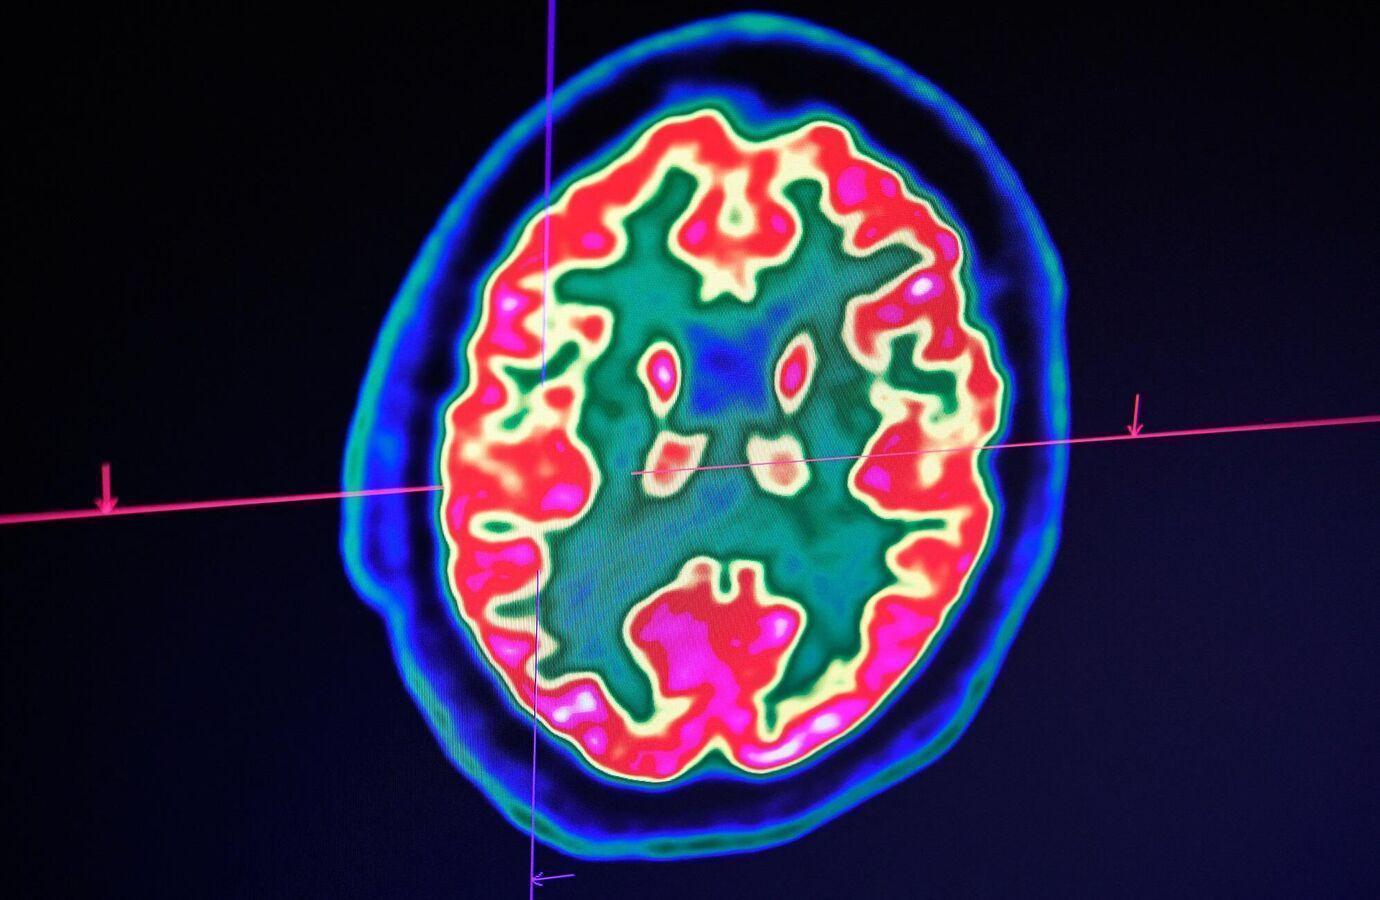

واكتشف فريق الدراسة، المنشورة في مجلة “Communications Medicine”، أنه بعد إجرائهم تحليلا شاملا لقشرة الدماغ، وجدوا أن مناطق معينة من الدماغ تشارك في تنظيم العواطف والإدراك وما إلى ذلك، تتغير مع مرور الوقت، نتيجة السكن في حي محروم من الناحية الاجتماعية والاقتصادية.

وقام الباحثون بالتحقيق في الروابط بين “مؤشر الحرمان في المنطقة” ونتائج التصوير العصبي على 4 مستويات من قشرة الدماغ لدى المشاركين، الذين خضعوا لنوعين محددين من فحص التصوير بالرنين المغناطيسي، والذي تم فحص نتائجه بعد ذلك.

وعن نتائج الدراسة، تقول كبيرة مؤلفيها، الطبيبة أربانا جوبتا، وهي المدير المشارك لمركز جودمان لوسكين ومدير مركز التصوير العصبي: “وجدنا أن عيوب الحي كانت مرتبطة بالاختلافات في البنية الدقيقة لقشرة الدماغ، وارتبطت بعض هذه الاختلافات بارتفاع مؤشر كتلة الجسم، كما ارتبطت بتناول كميات كبيرة من الأحماض الدهنية المتحولة الموجودة في الوجبات السريعة المقلية”.

وأضافت جوبتا أنه على وجه التحديد، يبدو أن الدراسة تشير إلى أن مناطق الدماغ المشاركة في “المكافأة والعاطفة واكتساب المعرفة والفهم، قد تتأثر بجوانب الحرمان في الحي، التي تسهم في السمنة”.